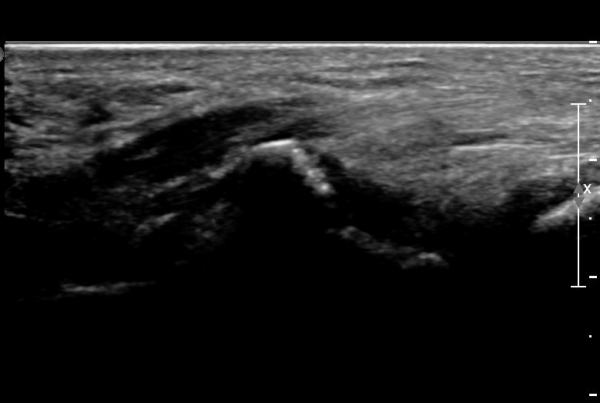

ÃÊÀ½ÆÄ°Ë»ç : ¼Õ¸ñ ¼ö±Ù°ü ±ÙÀ§ºÎ Ⱦ´Ü¸é°Ë»ç¿¡¼­ Äá¾Ë»À Ç¥ÃþÀ¸·Î ¾à°£ÀÇ ¿¬ºÎÁ¶Á÷ ºÎÁ¾ÀÌ °üÂûµÊ(»çÁø 1).

ŽÃËÀÚ¸¦ ¾à°£ ¸»´ÜÀ¸·Î À̵¿ÇÏ´Ï ¿¬ºÎÁ¶Á÷ ºÎÁ¾ÀÌ ´õ¿í ½ÉÇÏ°Ô °üÂûµÇ°í(»çÁø 2),